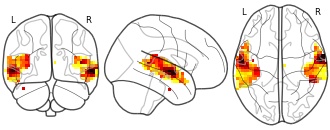

Data from: Mapping Lesions That Cause Psychosis to a Human Brain Circuit and...

EmailClick to copy linkLink copied Cite(2025). Mapping Lesions That Cause Psychosis to a Human Brain Circuit and Proposed Stimulation Target [Dataset]. http://identifiers.org/neurovault.collection:20510zipAvailable download formatsUnique identifierhttps://identifiers.org/neurovault.collection:20510Dataset updatedApr 29, 2025License

Cite(2025). Mapping Lesions That Cause Psychosis to a Human Brain Circuit and Proposed Stimulation Target [Dataset]. http://identifiers.org/neurovault.collection:20510zipAvailable download formatsUnique identifierhttps://identifiers.org/neurovault.collection:20510Dataset updatedApr 29, 2025LicenseCC0 1.0 Universal Public Domain Dedicationhttps://creativecommons.org/publicdomain/zero/1.0/

License information was derived automaticallyDescriptionA collection of 1 brain maps. Each brain map is a 3D array of values representing properties of the brain at different locations.

Collection description

Pines AR, Frandsen SB, Drew W, Meyer GM, Howard C, Palm ST, Schaper FLWVJ, Lin C, Butenko K, Ferguson MA, Friedrich MU, Grafman JH, Kappel AD, Neudorfer C, Rost NS, Sanderson LL, Taylor JJ, Wu O, Kletenik I, Vogel JW, Cohen AL, Horn A, Fox MD, Silbersweig D, Siddiqi SH. Mapping Lesions That Cause Psychosis to a Human Brain Circuit and Proposed Stimulation Target. JAMA Psychiatry. 2025 Apr 1;82(4):368-378.